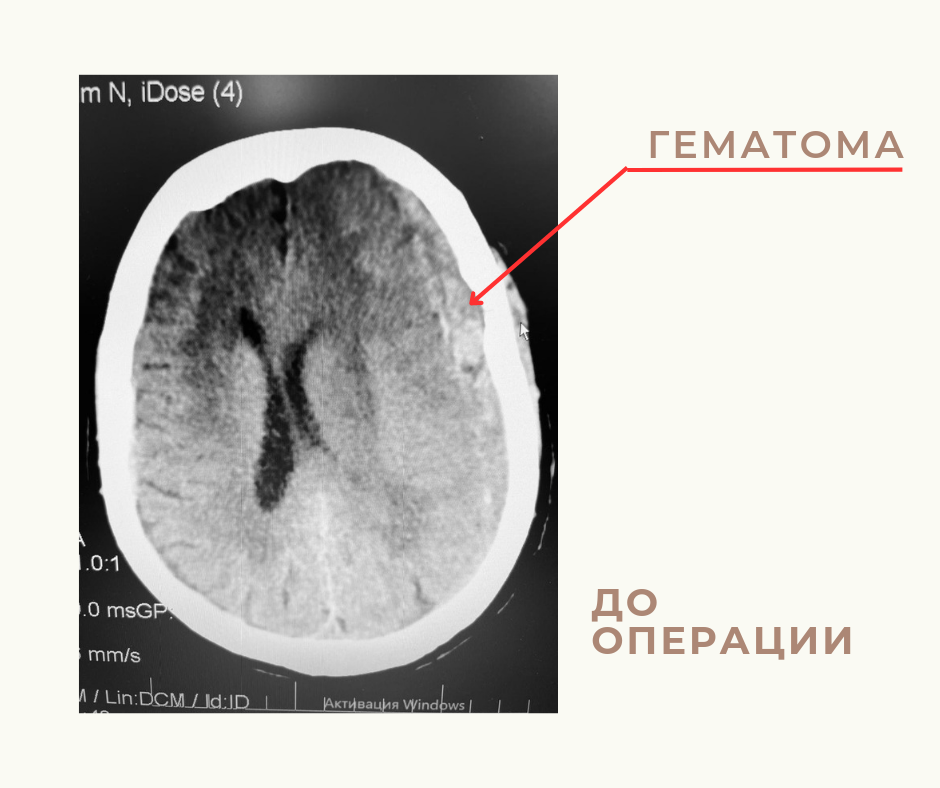

В первичное сосудистое отделение была доставлена 86-летняя пациентка в тяжелом состоянии. Точного времени, когда у больной произошел приступ, неизвестно - родственники обнаружили ее дома уже в бессознательном состоянии. По результатам обследования у пациентки диагностировали острое нарушение мозгового кровообращения. Компьютерная томография выявила нетравматическую субдуральную гематому в левой теменной области, отек вещества головного мозга.

Женщину срочно госпитализировали в нейрохирургическое отделение. Экстренную операцию провела дежурная бригада специалистов – врачи-нейрохирурги Менглибай Аджибаев и Руслан Мирзаев, анестезиолог-реаниматолог Евгения Усенова, операционная медицинская сестра Наталья Фабрикантова и анестезистка Флюра Зайнуллина. Пациентке выполнили резекционную трепанацию в левой лобно-теменно-височной области и удалили большую полушарную субдуральную гематому.

«Учитывая возраст, состояние пациентки было отягощено рядом сопутствующих заболеваний, - рассказал заведующий нейрохирургическим отделением ГКБ №3 им. С. М. Кирова Евгений Чечухин. - Операция прошла успешно. Объем гематомы составил 100 см3».